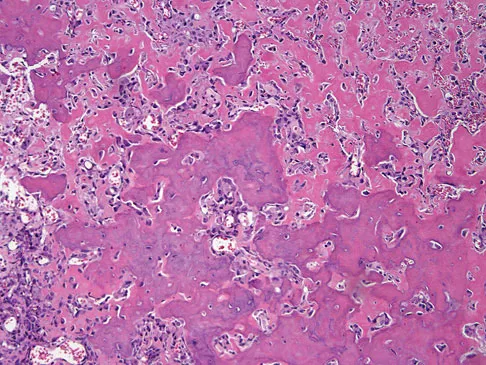

A 47-year-old woman has had a 1-month history of left hip and medial thigh pain that is exacerbated by sitting. Laboratory studies show a total protein level of 8.2 g/dL (normal 6.0 to 8.0) and an immunoglobulin G (IGG) level of 2,130 mg/dL (normal 562 to 1,835). A radiograph, CT scan, and biopsy specimen are shown in Figures 38a through 38c. What is the most likely diagnosis?

The laboratory studies and histology are both consistent with myeloma. Infection should show white blood cells other than plasma cells on histology. Lymphoma would show lymphocytes, not plasma cells. The lack of bone formation on the imaging studies and the lack of osteoid on histology rule out osteosarcoma. The cells have too much cytoplasm and nuclear chromatin to be Ewing's sarcoma cells.